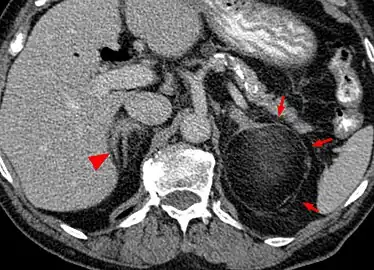

Myeloplipoma shown on a CT scan image

Most myelolipomas are unexpected findings on CT scans and MRI scans of the abdomen. They may sometimes be seen on a plain X-ray films.[4]

Fine needle aspiration may be performed to obtain cells for microscopic diagnosis.[1]